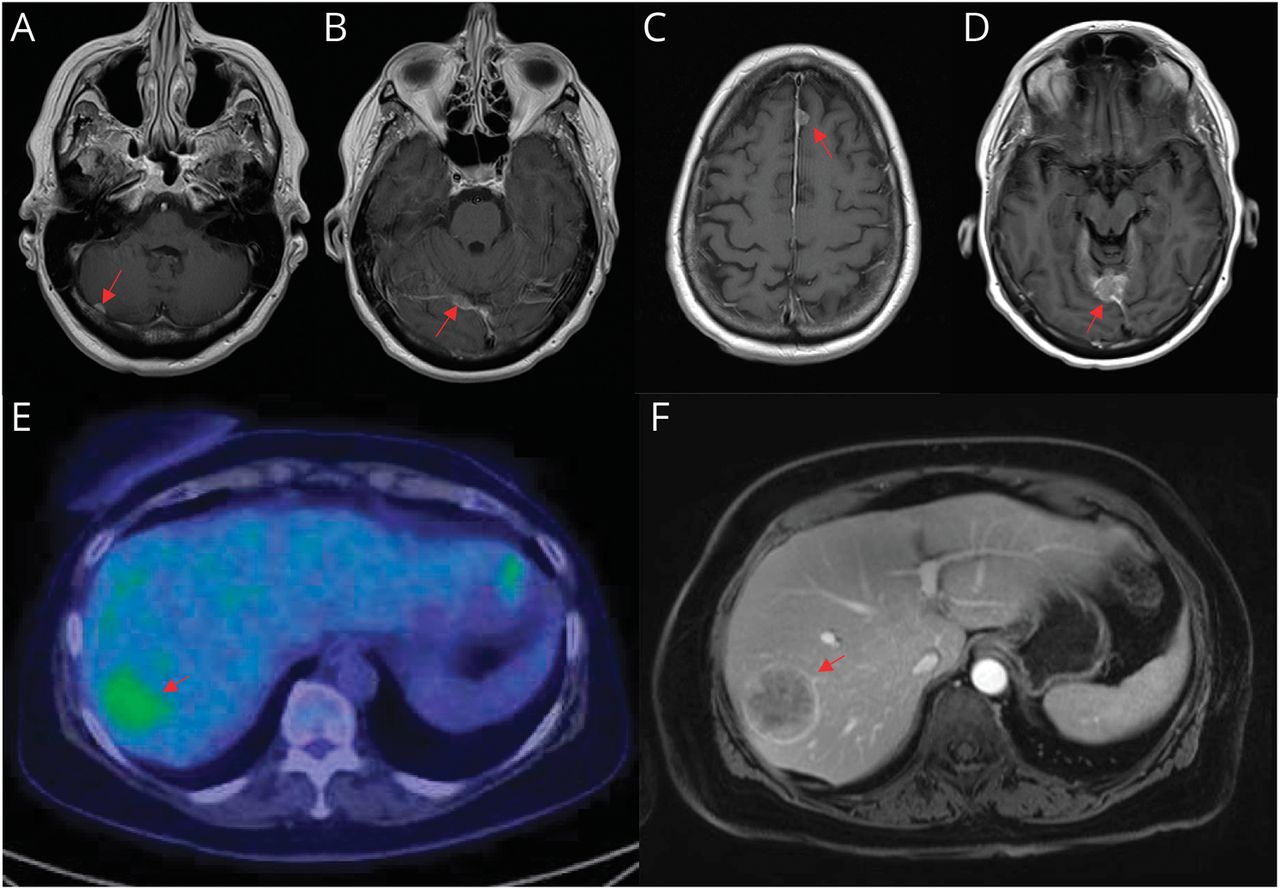

一个65岁的女人出现恶心、头痛、和视觉变化。核磁共振成像的大脑识别dural-based病变涉及正确的小脑,小脑幕,左前镰与脑膜瘤被认为是一致的(图中,得了)。由于不清楚影像学表现和临床症状之间的联系,监视被推荐。后续是不经意间延迟。重复成像在7个月显示扩大幕的病变,接受伽玛刀放射治疗(GKRS) (图D)。进一步发展了小脑病变的切除。肿瘤细胞呈阳性STAT6免疫组织化学,建立单独纤维肿瘤(SFT)作为诊断。磁共振发现fluorodeoxyglucose-avid肝损伤,活检证实STAT6, CD34, synaptophysin-positive转移SFT (图中,E-F)。附加GKRS后,系统性治疗舒尼替就开始了。sft间质肿瘤主要影响年轻人,应该包括微分的硬脑膜的基础病变。1鉴于颅外转移倾向,全身成像应该在建立组织获得诊断。2

Postcontrast t1加权磁共振轴显示小脑病变涉及正确的(A),幕的传单(B),左前镰(C)。(D) Postcontrast t1加权磁共振轴向展示增加对幕的病变的大小。pet - ct机(E)显示病变在上级后肝右叶。(F) MRI显示肝转移。